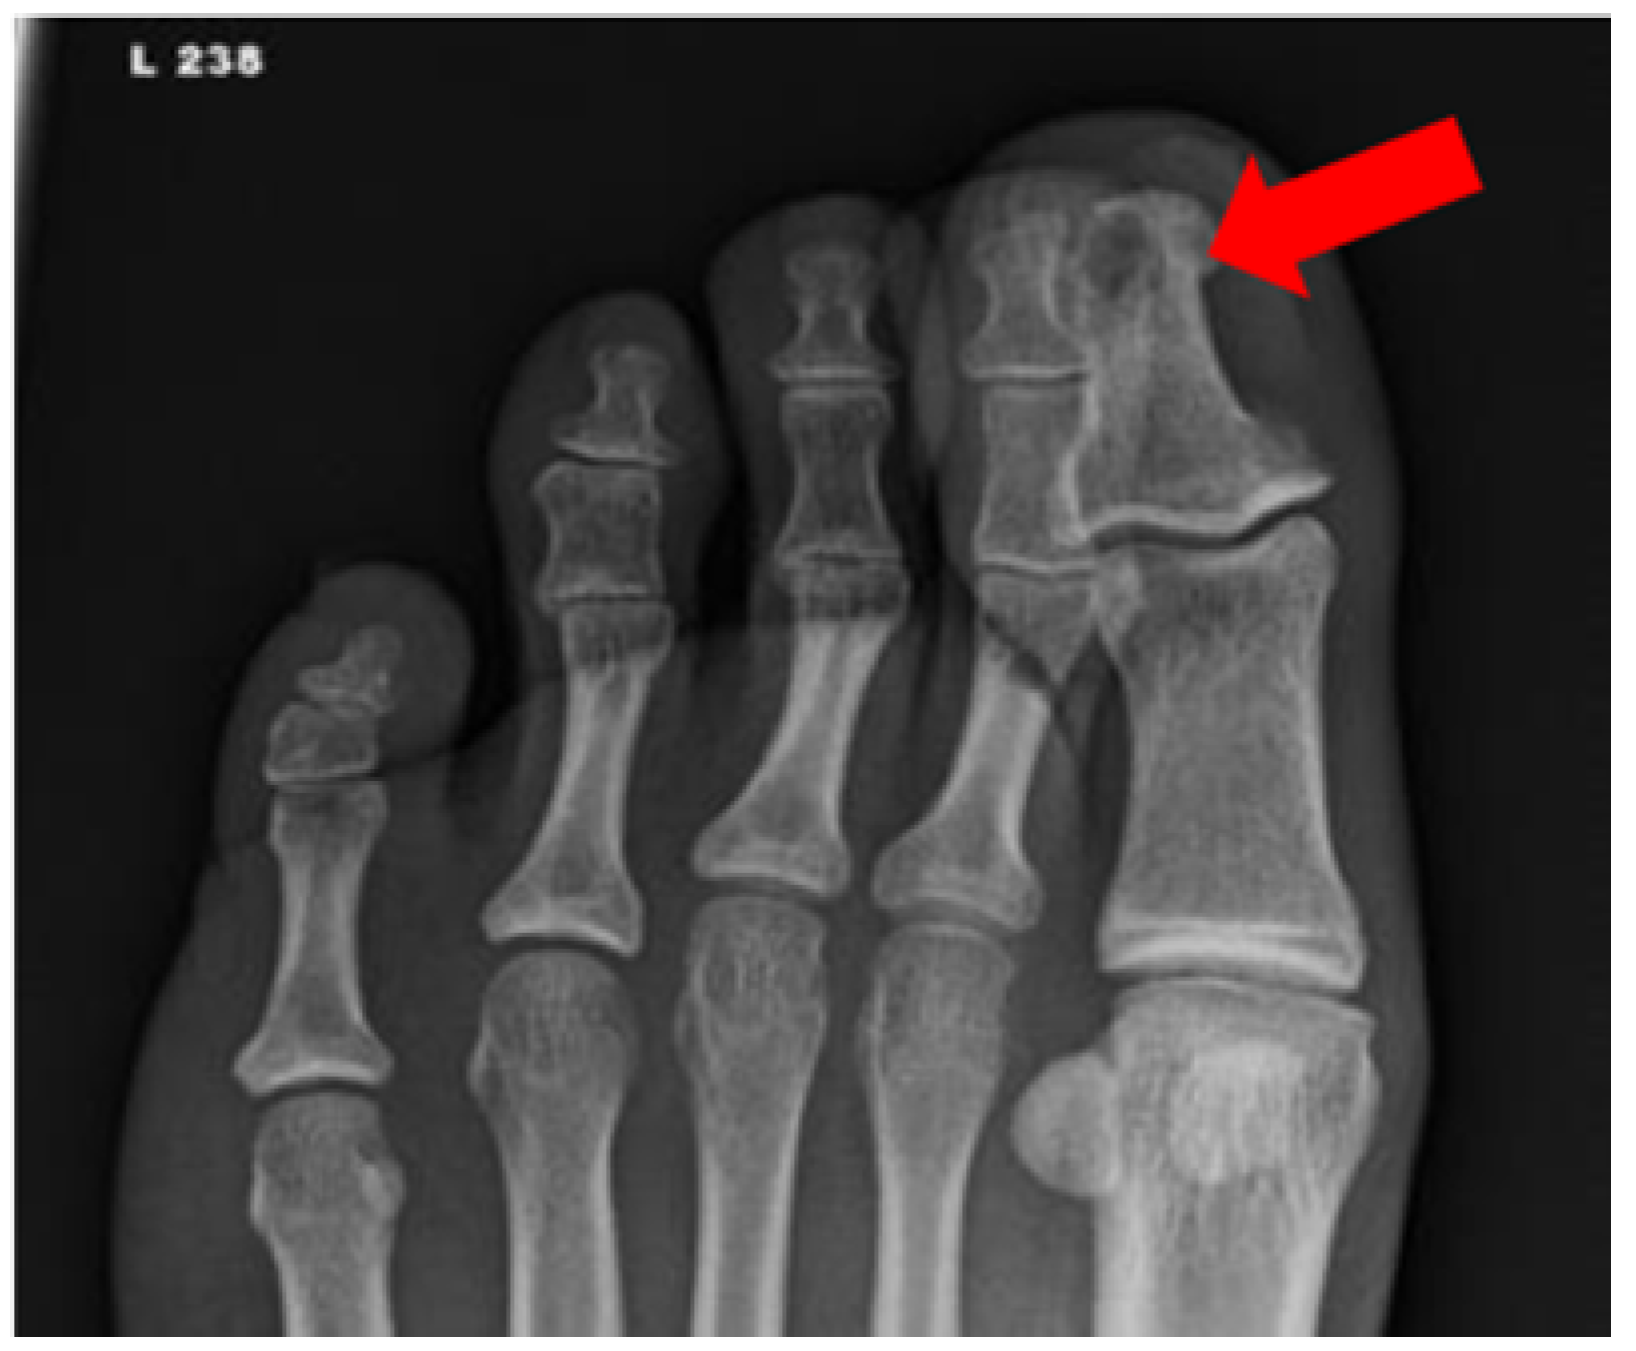

- Álvaro-Afonso, F.J.; Lázaro-Martínez, J.L.; García-Morales, E.; García-Álvarez, Y.; Sanz-Corbalán, I.; Molines-Barroso, R.J. Cortical disruption is the most reliable and accurate plain radiographic sign in the diagnosis of diabetic foot osteomyelitis. Diabet. Med. 2019, 36, 258–259. [Google Scholar] [CrossRef]